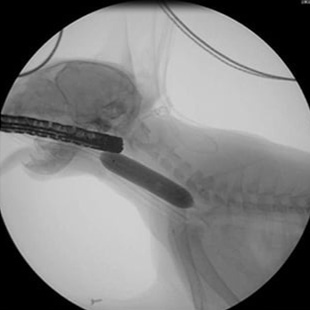

· 기관 스텐트 장착 전

· 기관 스텐트 장착 후